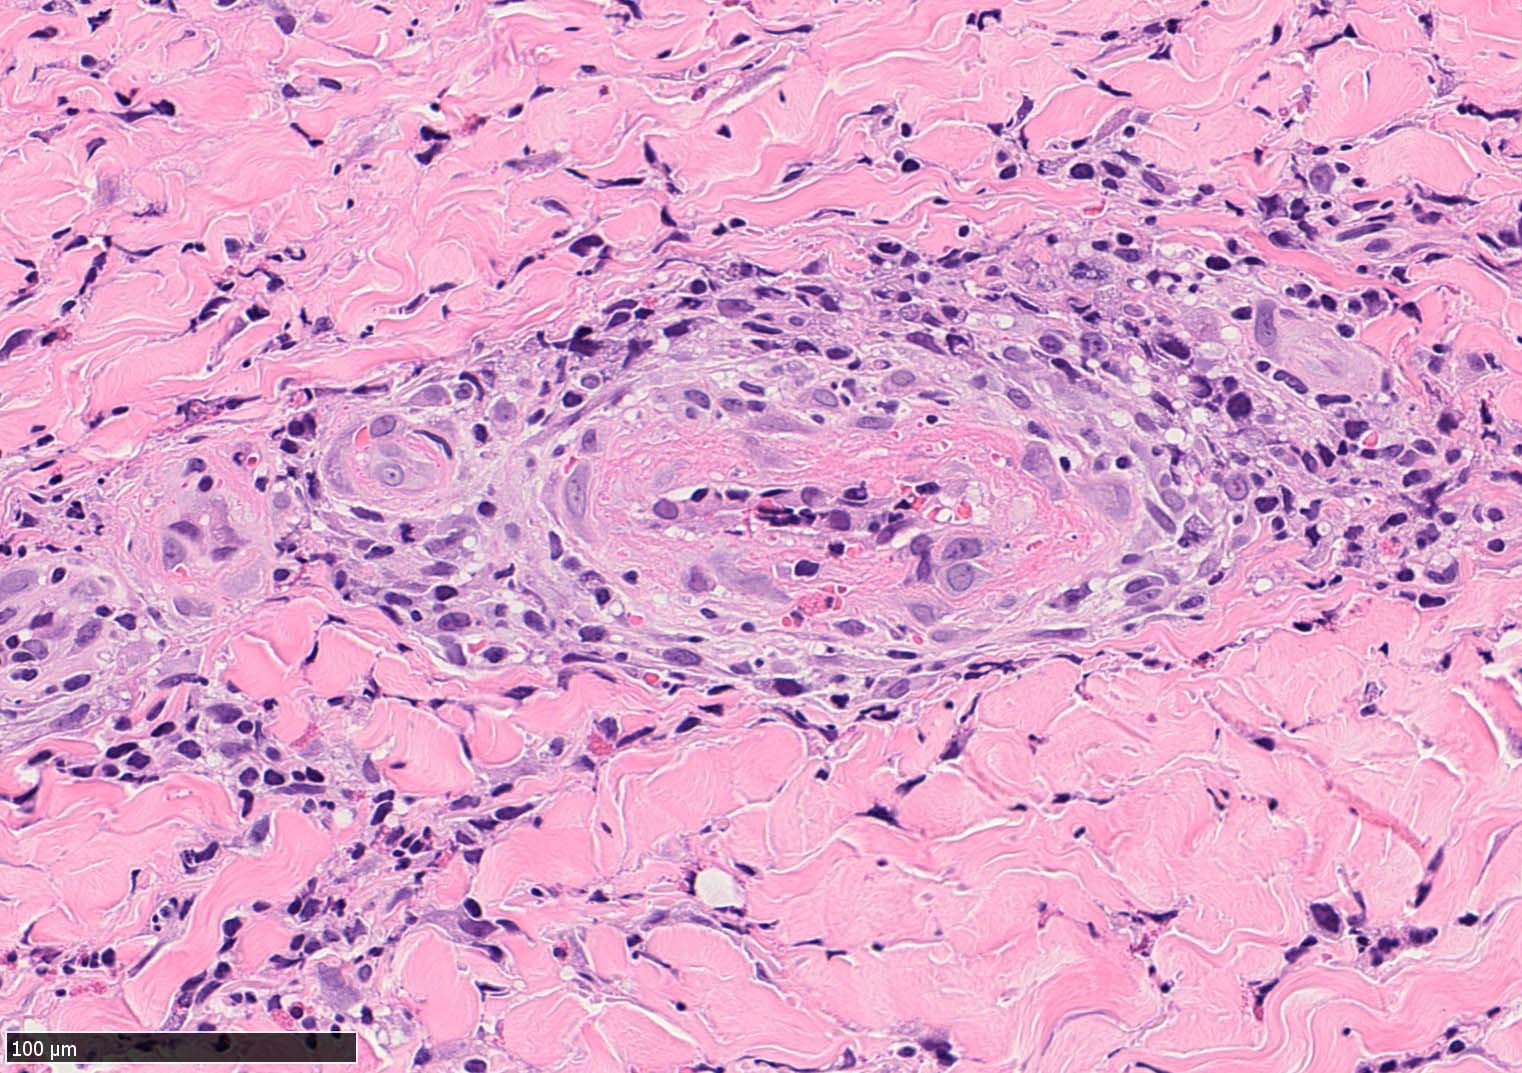

IWT-case03 マダニに咬まれた. 自分で虫体を除去したが傷がびらん化し, 発熱を来したため, 来院する.

痂皮の下に硝子様凝固物があり, 周囲には壊死組織が形成されている. 近傍の細血管には凝固物による閉塞の所見があるように見える. 連続する細血管には, fibrinoid necrosisを呈する壊死性血管炎が認められる.